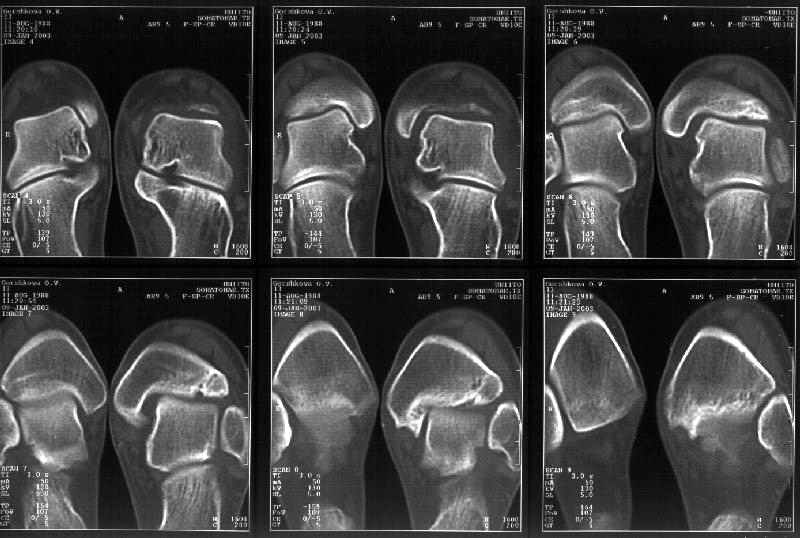

На следующий день пациентке сделали КТ. Может быть, после просмотра картинки будут другие предложения? Не убрать ли ве-таки этот фрагмент

позади внутренней лодыжки, который оттесняет таран кнаружи?

Думаю, КТ прочитан не верно. Задняя часть медиального маллеола, в сущности уже часть заднего маллеола стоит на месте и трогать её не следует. Передняя часть маллеола на 3-4 мм удалена от тарана. Сравните с пространством между

латеральным маллеолом и тараном. В норме все три должны быть одинаковы: между тараном и латеральным, задним и медиальным. Это главное условие устойчивого сидения тарана в голеностопном суставе.

Все-таки она как раз была была отколота и вместе с тараном смещена латерально.

Внутренняя лодыжка не была сломана, она как была на своем месте, так там и находится. Это таран от нее отдавлен кнаружи смщенным в его сторону фрагментом позади внутренней лодыжки. За счет чего и есть проявления нестабильности связок.

Вот и проблема. Восстанавливать ли эту равномерность сейчас, и если да, то как. Вот точка зрения коллеги из Штатов:

======================================================

Interesting case. thanks for the ct cuts. now it is real clear that there is a posterior medial maleolar fragment displaced into the joint forcing the talus laterally. My first inclination in this young girl is to debride out the displaced fragment. The difficult part will be visualization ot know how much to take. My approach would be through an oblique medial malleolar osteotomy and hinge the distal malleolus away from the talus leaving the deep deltoid intact. this way you could easily view the whole articular surface of the medial gutter. I would debride the prominent bone back slightly beyond the level of the normal

malleolar surface. The osteotomy may also help reduce the widened mortise. I don't see anything i would do to the syndesmosis area nor any

significant lenght differences between the fibula and tibia laterally form the proximal tibia fracture.

John Early MD

U Texas Southwestern Med Ctr

Dallas, Texas

john.early@utsouthwestern.edu

тибиальной основы. По мне, КТ это совершенно ясно показывает.

Идея шлифовать "выступ" медиально-задней поверхности, поддержанная техасским ковбоем, на мой взгляд чревата катострофой, т.к. неверна по пониманию биомеханике прошлого ляпсуса, чрезвычайно сложна по доступу. Я могу чётко

прогнозировать, что эта процедура усилить неустойчивость голеностопа, повредит окончательно ростовой потенциал дистальной тибии и приведёт девочку к тяжёлой инвалидности. По моему это тот случай, когда не за то папа сына

бил что в карты играл, а зато что отыгрывался. Но Вы вольны оставаться при своём мнении.

> тибиальной основы. По мне, КТ это совершенно ясно показывает.

Мне в тоже время совершенно ясно видно по той же КТ, по 4 срезам, расположенным в центре и вверху пленки, что перелома внутренней лодыжки не было, в следующем собщении я приложу увеличенный фрагмент томограммы. А к этому письму прилагаю увеличеный фрагмент послеоперационной рентгенограммы, где выделил отколотый фрагмент

позади внутренней лодыжки. И он, как я вижу, находится между стержнем и тараном. А перелома внутренней лодыжки, и тем более смещения, IMHO

не определяется.

Здесь 4 среза, начиная от основания лодыжки и проксимальнее. Где, по Вашему мнению, проходит линия перелома, отделяющая переднюю часть внутренней лодыжки от большеберцовой кости? Заранее спасибо.